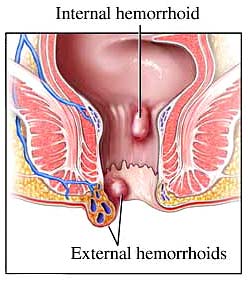

هموروئید عبارت است از بالشتک های عروقی طبیعی در کانال مقعد که به کنترل دفع کمک میکنند.هموروییدها وقتی ورم میکنند یا ملتهب میشوند غیرطبیعی میشوند.هموروئیدها دو نوع هستند: داخلی و خارجی

هموروئید داخلی

هموروئید داخلی در بالای خط دندانه ای است وبا اپی تلیوم ستونی پوشانده شده و رسپتورهای درد ندارد.انها در سال ۱۹۸۵ به ۴ دسته بر اساس درجه پرولاپس تقسیم شدند

هموروئید خارجی

این هموروئیدها زیر خط دندانه ای هستند.در قسمت فوقانی تر با انودرم و در قسمت پایینتر با پوست پوشیده شده اند.هردو قسمت به درد و حرارت حساس هستند.

هموروئید ترومبوزه

هموروئیدهای ترومبوزه که بصورت برآمدگی کبود رنگ و دردناک در آنودرم دیده میشوند,48 تا 72 ساعت درد شدید و ناراحت کننده ایجاد می کنند و بعد از آن درد کاهش می یابد. در صورتیکه بیمار در مرحله ابتدایی مراجعه نماید بهترین درمان هموروئید کتومی می باشد ولی اگر مدتی از شروع درد می گذرد و درد در حال کاهش باشد می توان درمان دارویی را انتخاب کرد.